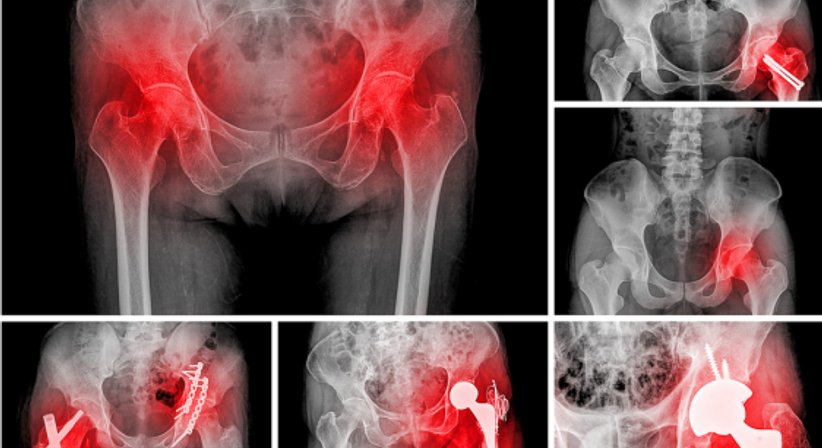

Neben dem Knie zählt die Hüfte zu einem der am häufigsten orthopädisch behandelten Gelenke. Die Hüfte kann von vielen verschiedenen Krankheiten betroffen sein, eine davon ist die Hüftarthrose (Coxarthrose), eine degenerative Erkrankung vom Hüftgelenk und die mitunter am häufigsten auftretende Arthrose beim Menschen.

Viele, vor allem ältere Patienten, leiden im Laufe des Lebens unter den mit Hüftarthrose einhergehenden Beschwerden, darunter morgendliche Anlaufschmerzen im Bereich vom Hüftgelenk, belastungsabhängige Hüftschmerzen, Ruhe- und Nachtschmerzen im Hüftbereich, ausstrahlende Schmerzen ins Knie, Versteifung, Knack- und Reibegeräusche sowie Gehbeschwerden, die schließlich dazu führen, dass die maximale schmerzfreie Gehstrecke stetig kürzer wird bis schließlich nur noch sehr kurze Strecken ohne Schmerzen zurückgelegt werden können.

Behandlung der Hüftarthrose